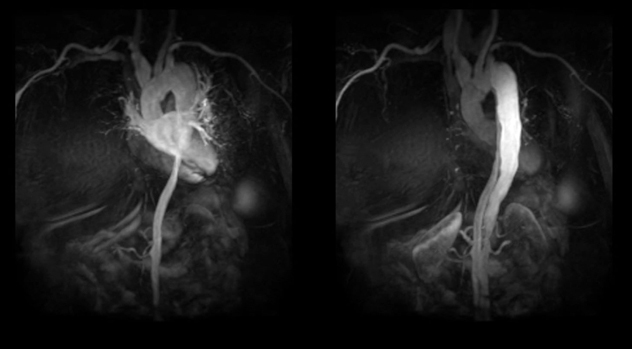

Test de Isquemia

La opción de la RMC en la evaluación de isquemia miocárdica, es principalmente útil en pacientes incapaces de ejercitarse hasta cargas de trabajo adecuadas y en aquellos que tienen trastornos de conducción en el ECG. Además es importante remarcar, que junto a las excelentes condiciones que posee la RMC para la detección de isquemia miocárdica, se agregan los datos adicionales que aporta sobre función y estructura cardíaca. Esto hace que la RMC sea una herramienta muy útil para el estudio de las cardiopatías congénitas, las miocardiopatías, y para valorar la presencia de viabilidad miocárdica.

Reforzamiento tardío

La RM cuenta con una técnica de gran utilidad en la evaluación de viabilidad que determina zonas de necrosis y su extensión posterior a la administración de material de contraste al aplicar una secuencia inversión recuperación que anula el tejido miocárdico normal, lo cual favorece el contraste de las zonas que permanecen hiperintensas.